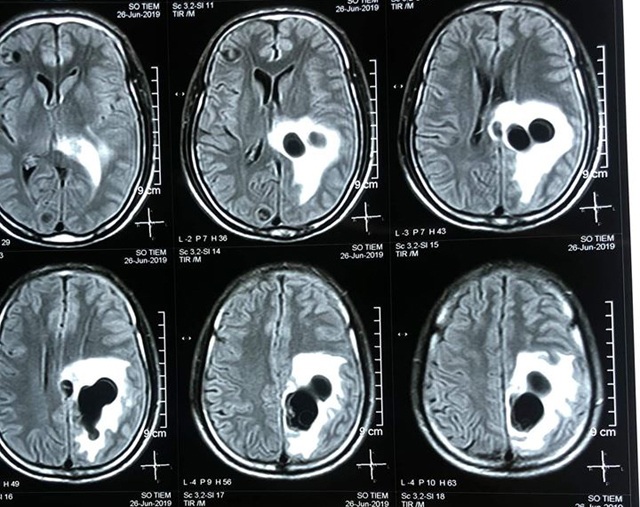

Kết quả chụp CT cho thấy có 5 ổ sán nằm rải rác trong não bệnh nhân, trong đó có một ổ sán lớn trên đỉnh, gây phù não. Bệnh nhân được chỉ định can thiệp ngoại khoa để lấy trọn vẹn ổ nang sán khỏi não. Sau mổ, bệnh nhân hồi phục, tỉnh táo, không liệt, đi lại và sinh hoạt bình thường.